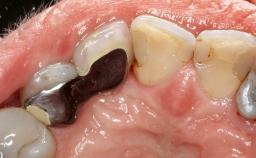

A 30-year-old patient presented at our clinic with a chief complaint of pain in her endodontically treated right maxillary central incisor (tooth 11) with a post-and-core and a fixed single crown. She had a very high lip line, a medium to thin soft-tissue phenotype, and a medium scalloped gingival contour. She also had high esthetic expectations because of her young age and beautiful smile. However, her expectations were realistic and she understood the risks of the treatment. At the initial clinical examination there was a slight mobility of tooth 11; no fistula was observed. The patient also had a single crown on the adjacent tooth 21. Both restorations were old and esthetically deficient. A digital periapical radiograph showed a very small periapical radiolucency, a thick intraradicular post, and no separation between root fragments.